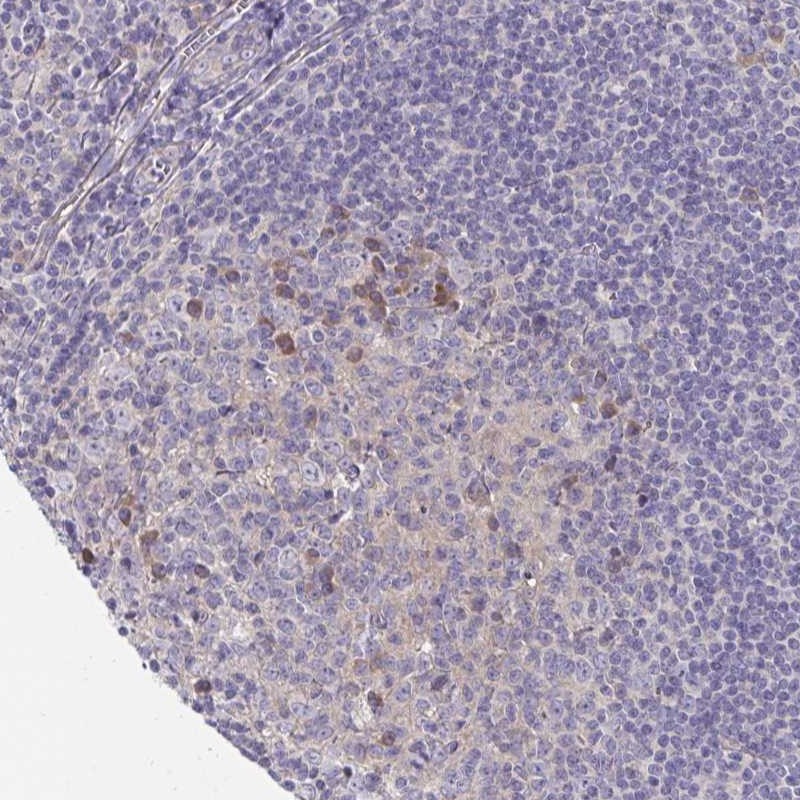

Immunohistochemical staining of human tonsil shows moderate cytoplasmic positivity in subset of germinal center cells.